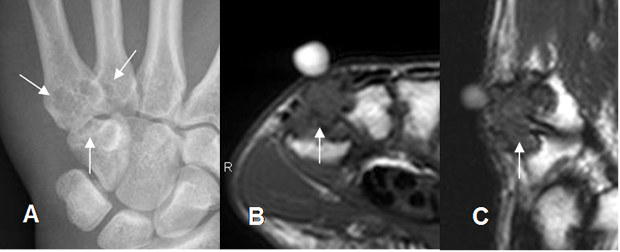

Fig 124 B. Tumor de células gigantes.

A: Rx AP. Erosión de bordes escleróticos, en las bases del 4º y 5º metacarpiano y el hueso ganchoso. B: RM axial en T1 y C: RM sagital en T2. Masa de tejidos blandos hipointensa en ambas secuencias, que erosiona el hueso, por tumor de células gigantes.